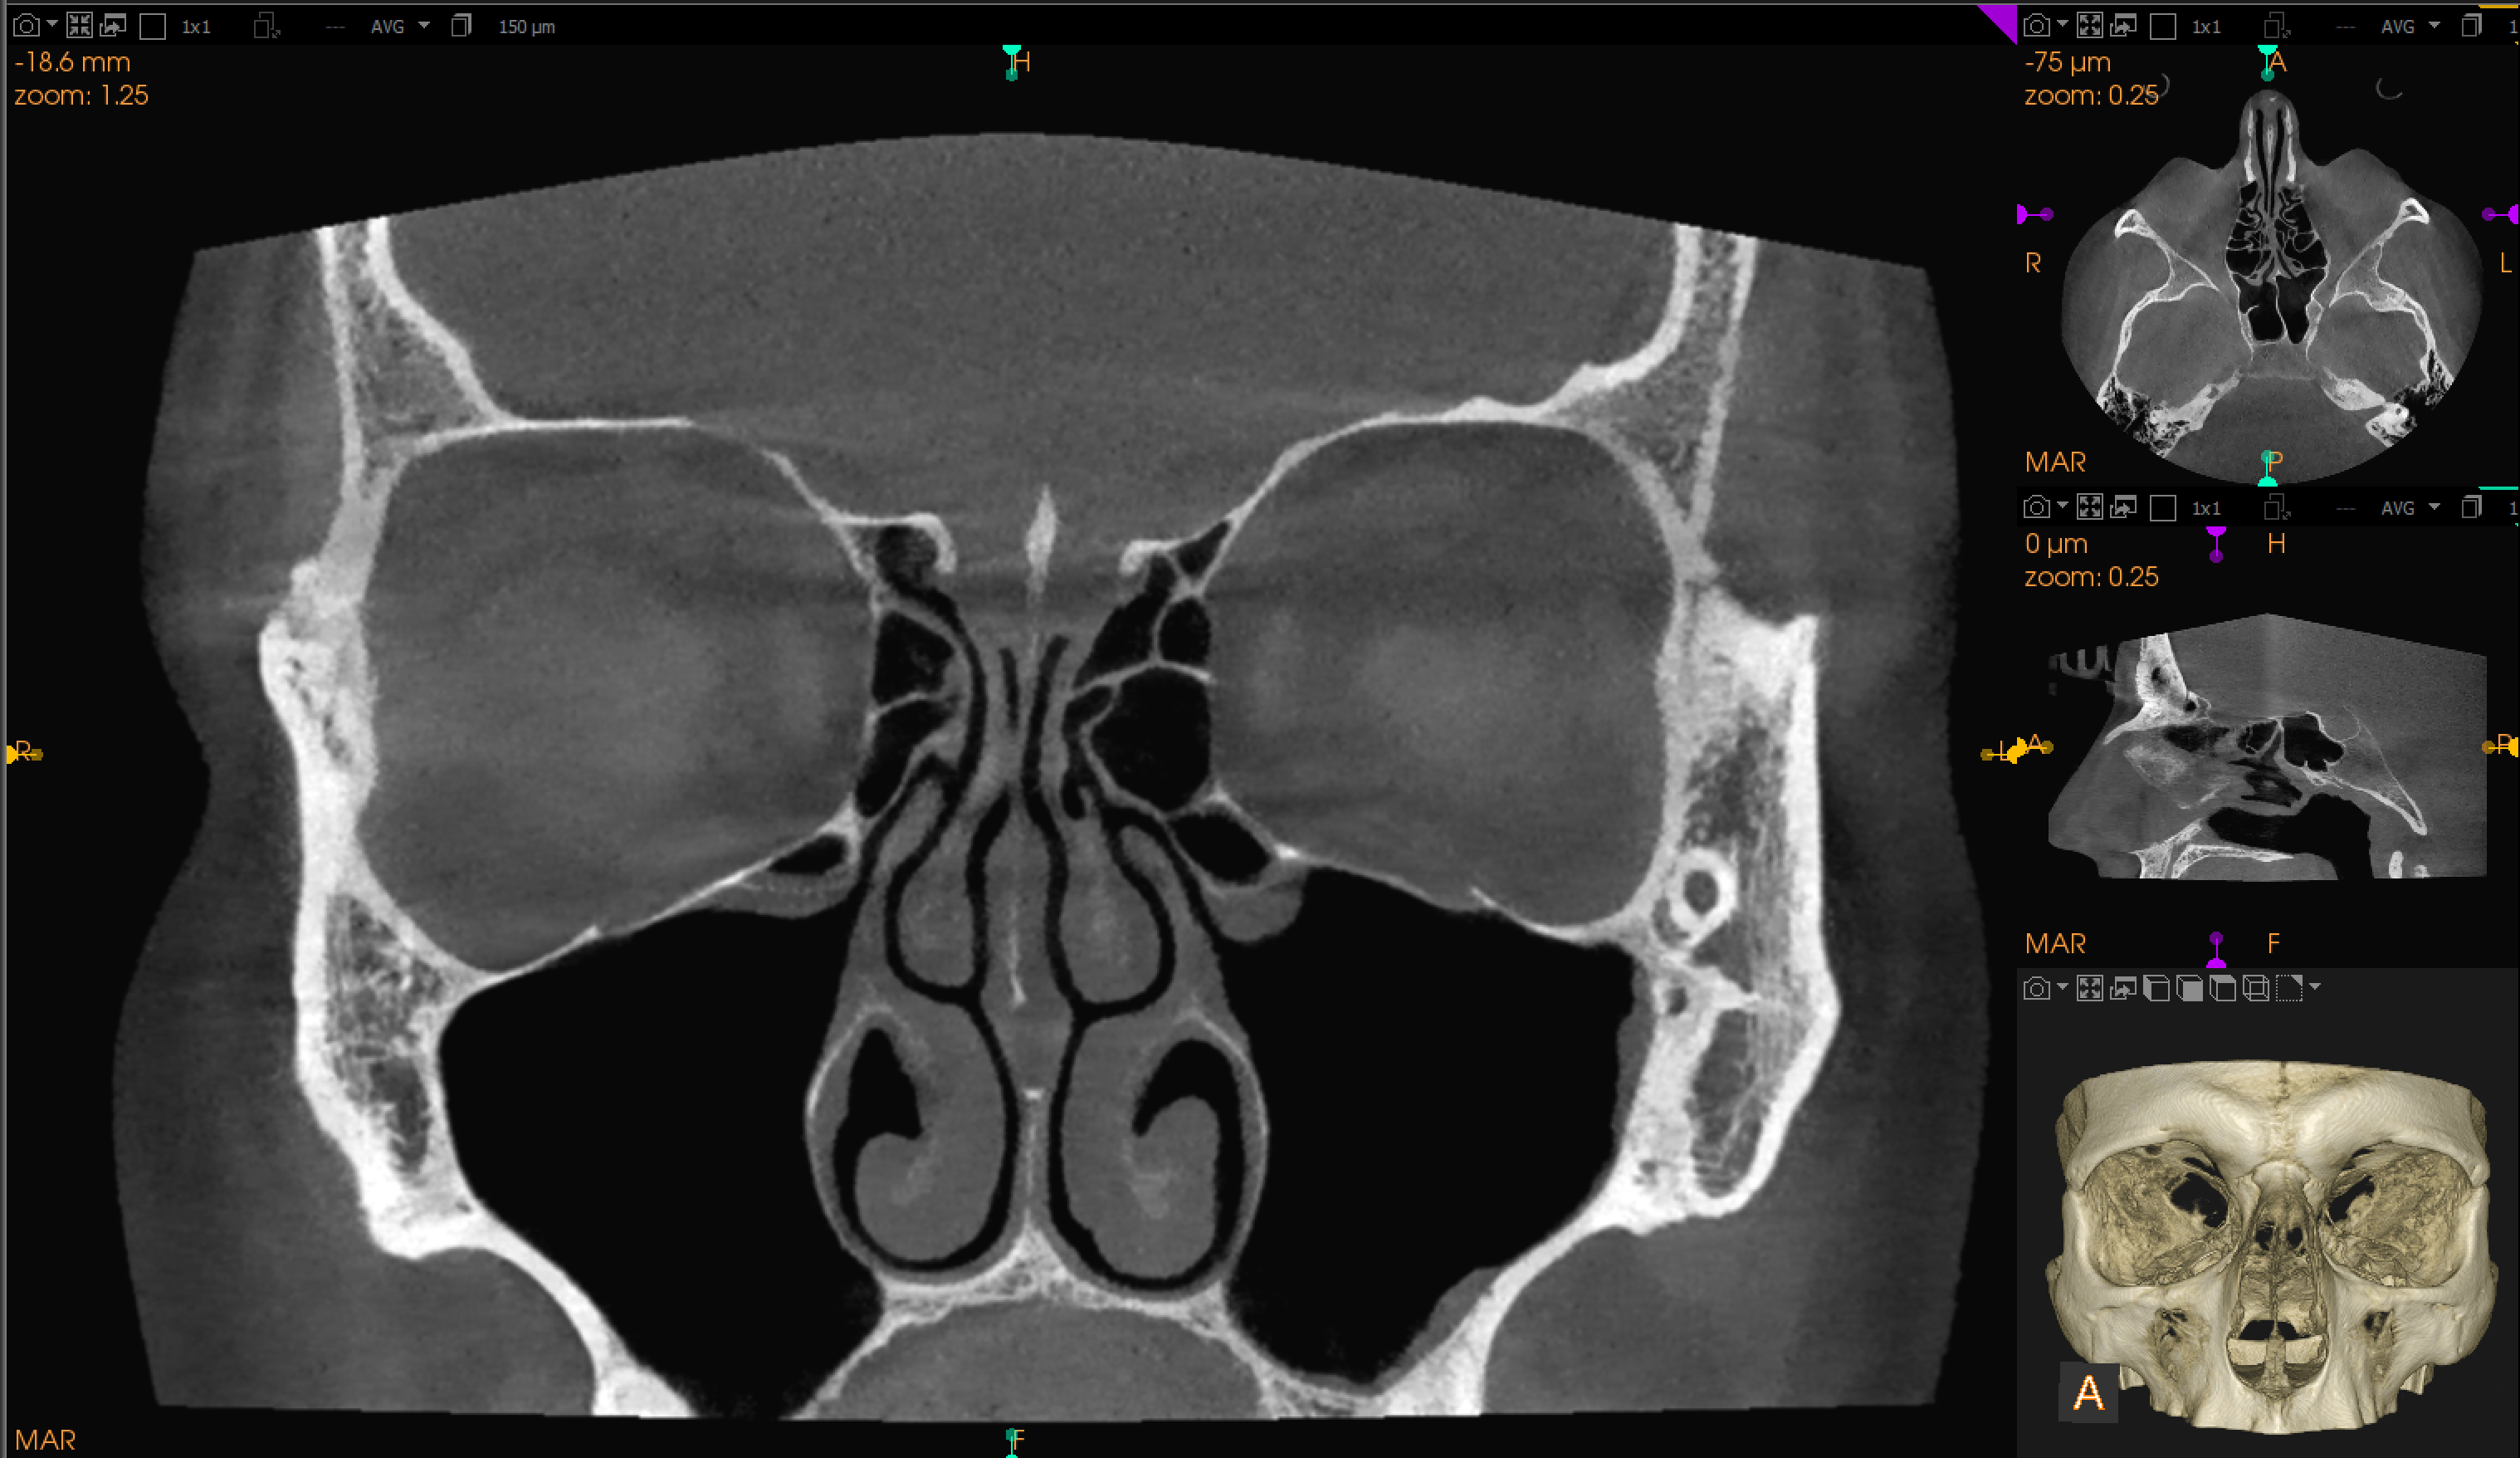

Tomography of the sinuses

CBCT (Cone Beam Computed Tomography) of the sinuses is a specialized X-ray imaging procedure that provides detailed 3D images of the sinus anatomy and any existing pathologies. The sinuses are air-filled spaces located within the bones of the skull and face, which include the frontal, maxillary, ethmoid, and sphenoid sinuses.

Using a cone-shaped X-ray beam, this technology provides detailed images of the bone structure, tooth positioning, and surrounding anatomy of these areas, allowing for enhanced diagnosis, treatment planning, and evaluation in dental and maxillofacial applications. This comprehensive 3D view offers detailed insights that surpass traditional 2D radiographs.

- High-Resolution 3D Images: Detailed visualization of the dental and skeletal structures, which can be rotated and analyzed from different angles.